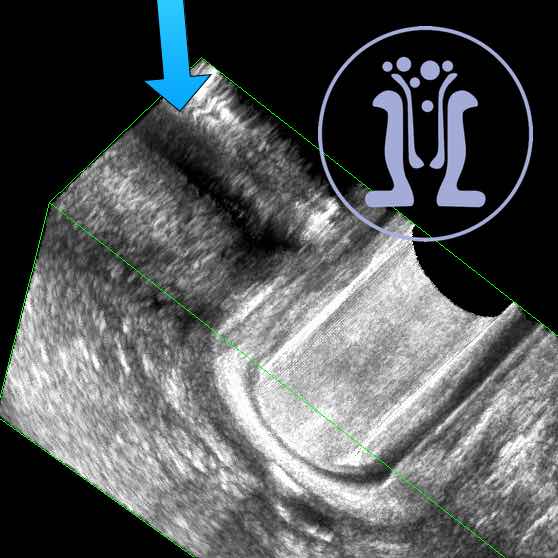

54 ετών κύριος αναφέρει εκροή πύου και φλεγμονής στη περίπρωκτικη περιοχη από 5 μήνες. Κλινικά ανευρέθηκε δερματικό στόμιο στην 3η ώρα. Στη δακτυλική εξέταση ανευρέθηκε ευμέγεθες στόμιο στην 6 ώρα. Με τη σκιαγράφηση του συριγγίου, το ενδοπρωκτικό υπερηχογράφημα επιβεβαιωσε την θέση του πρωκτικού στομίου και ταυτόχρονα έδειξε υψηλό συρίγγιο στην 6η ώρα με επέκταση έως 5 cm από το δακτύλιο του πρωκτού πίσω από την λήκυθο του ορθού.